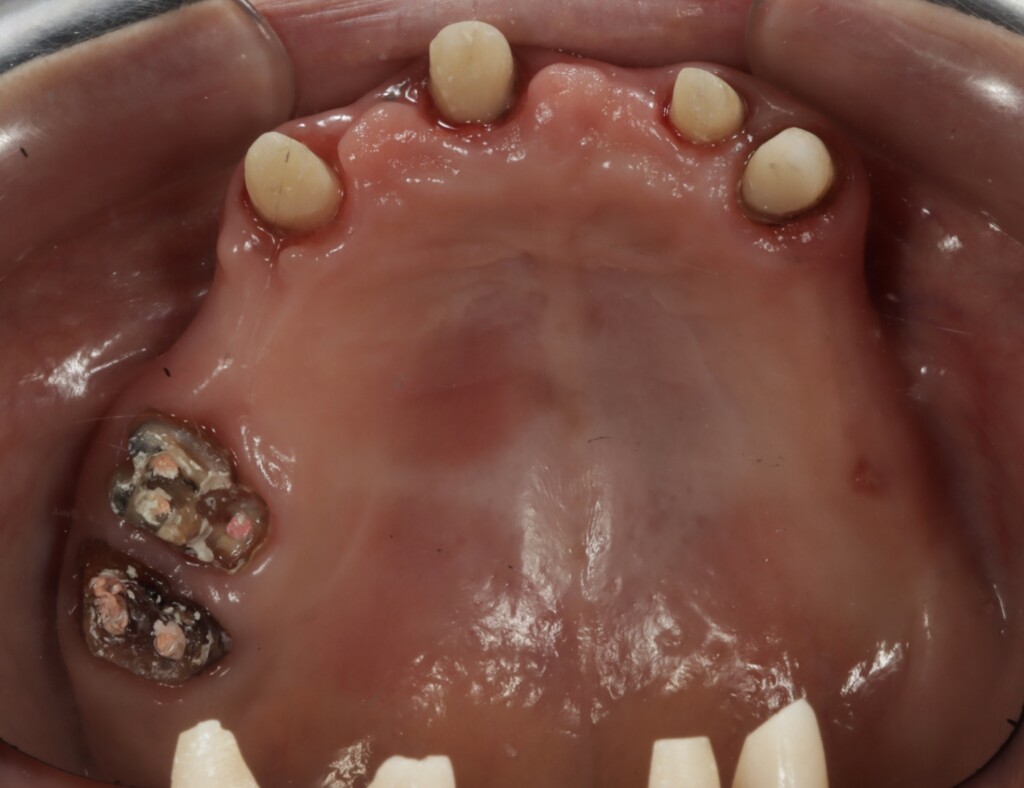

写真3:下顎の歯ぐきの状態

仮歯を外した状態(上顎前歯は土台が立っている)

上顎前歯部は健全歯質が縁上にほとんどない

右上奥歯も健全歯質が少ない

上顎の残っている歯は、これまでブリッジや被せもので連結されていたため分かりにくい状態でしたが、詳しく評価を行ったところ、左上の犬歯(糸切り歯)を除き、いずれの歯にも動揺が認められました。また、骨に埋まっている部分(支持組織)も少なく、歯を支える力が低下している状態でした。この点については、治療開始前の検査の段階である程度予測はできていましたが、実際には歯ぐきより上に十分な健全歯質も残っていない状況でした。このような歯に対して、ブリッジやクラウンのように歯へ大きな負担がかかる治療方法を選択し、さらに部分入れ歯の留め金をかける設計とした場合、負担が集中し、状態の悪化を招く可能性があります。そのため今回は、支える力が低下している歯への負担をできる限り抑える設計として、磁性アタッチメントを用いた入れ歯をご提案しました。